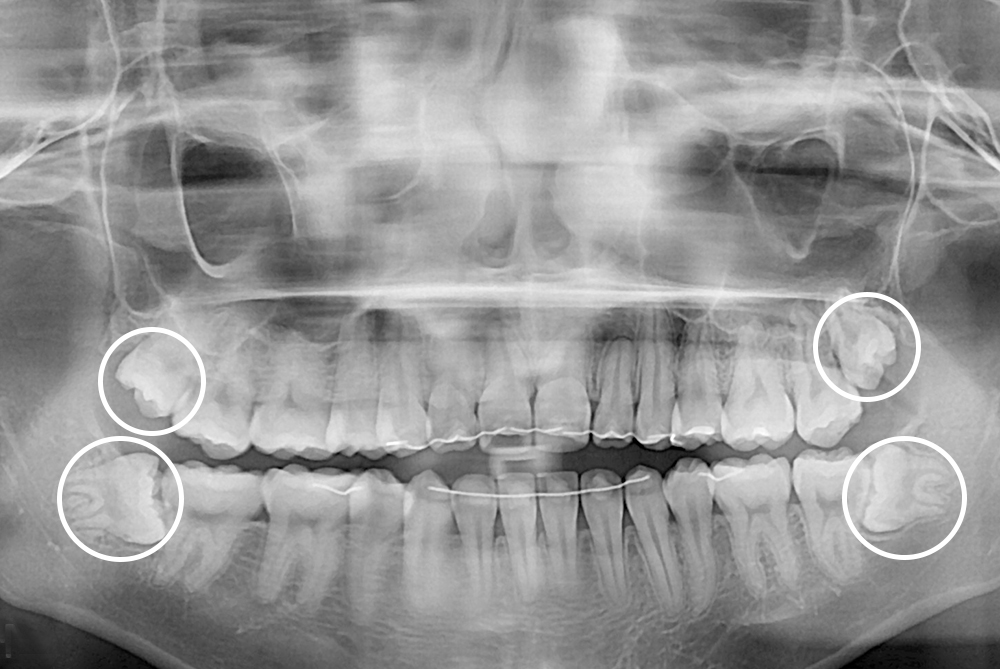

[사랑니] 매복 사랑니 발치

치료후 : 2019-06-28

세종치과는 구강악안면외과학 박사이신 원장님이 발치하는 치과입니다.